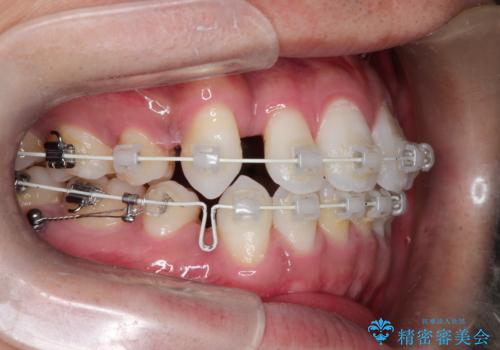

抜歯によって作られたスペースを利用し、前歯を後方に維持したまま、ガタついている歯を一つひとつ正しい位置へと整列させていきました。

審美ワイヤーを用いることで、歯の根元から角度を精密にコントロールし、前歯が前方に傾斜するのを防ぎながらスペースを閉じていきました。これにより、口元のボリュームを維持したまま、美しいアーチ状の歯並びを構築することが可能となりました。